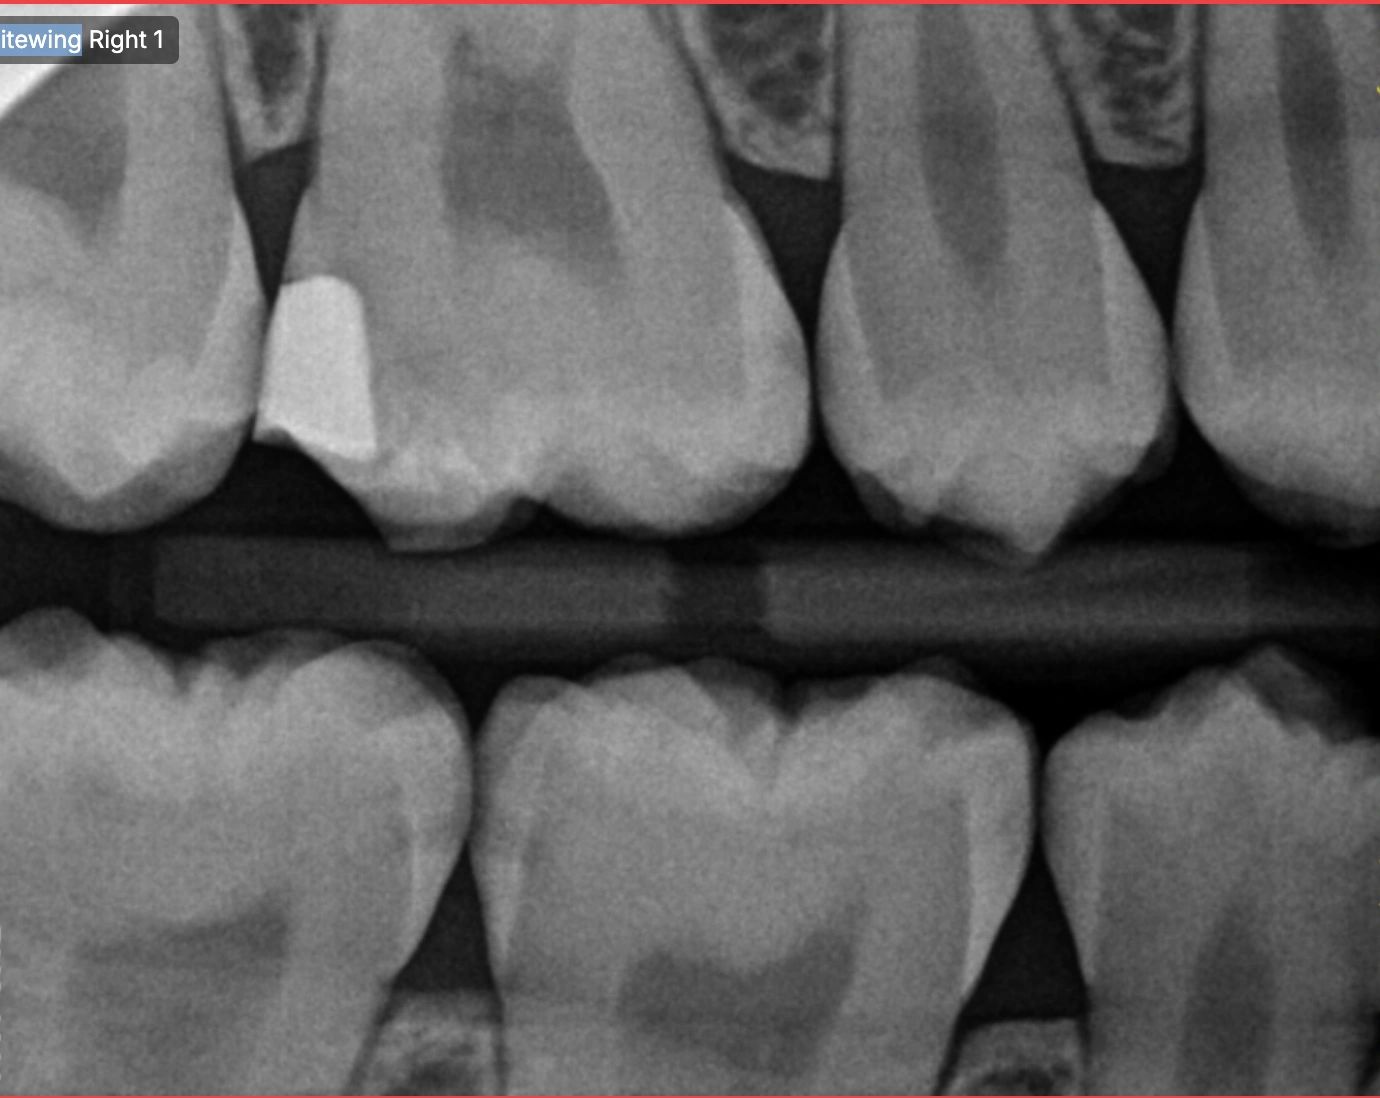

Early decay detection using a custom expert trained AI model is the foundation of our software solution. Catching decay early helps reduce costs for the patient and insurance whilst avoiding invasive dental treatment.

After decay is detected, treatment predictions are given. Whether it be invasive dentistry or non invasive dentistry. The patient will be given options on conservative treatment.